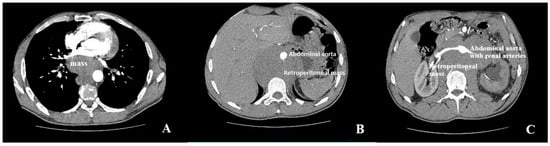

Extrinsic Left Atrial Compression: An Echocardiography-Guided Diagnosis Illustrated by Two Clinical Cases and a Structured Review of Published Cases

Background: Extrinsic compression of the left atrium (LA) is a rare and underrecognized condition that may result in significant hemodynamic compromise and atrial arrhythmias. The available evidence has been largely limited to isolated case reports and small case series, and clinical awareness has remained low. Methods: We performed a structured review of published case reports and case series indexed in PubMed between 2016 and 2026 describing extracardiac LA compression. A predefined and reproducible literature search strategy with explicit eligibility criteria was applied. The structured review included 22 publications reporting 23 individual cases of LA compression; in addition, two institutional cases with distinct etiologies were presented separately. Demographic characteristics, presenting symptoms, diagnostic modalities, complications, management strategies, and outcomes were synthesized descriptively. Results: The structured review identified gastroesophageal disorders, particularly hiatal hernia, as the most frequent etiology, followed by vascular, mediastinal, malignant, and musculoskeletal causes. Dyspnea was the most common presenting symptom, while hemodynamic compromise, pulmonary edema, and atrial arrhythmia represented the most frequent complications. Transthoracic echocardiography was the initial diagnostic modality in all reported cases, with computed tomography required for definitive etiological diagnosis. The two institutional cases illustrated both a common cause, hiatal hernia mimicking intracardiac mass, and a rare, aggressive malignant cause with extensive mediastinal involvement. Conclusions: Extrinsic LA compression arises from diverse extracardiac pathologies and may be clinically severe. Transthoracic echocardiography can serve as a pivotal first-line tool for early recognition and differentiation from intracardiac masses, while cross-sectional imaging is essential for etiological clarification. By integrating institutional experience with a structured synthesis of published cases, this review can provide practical insights to support timely diagnosis and management of this potentially life-threatening condition.